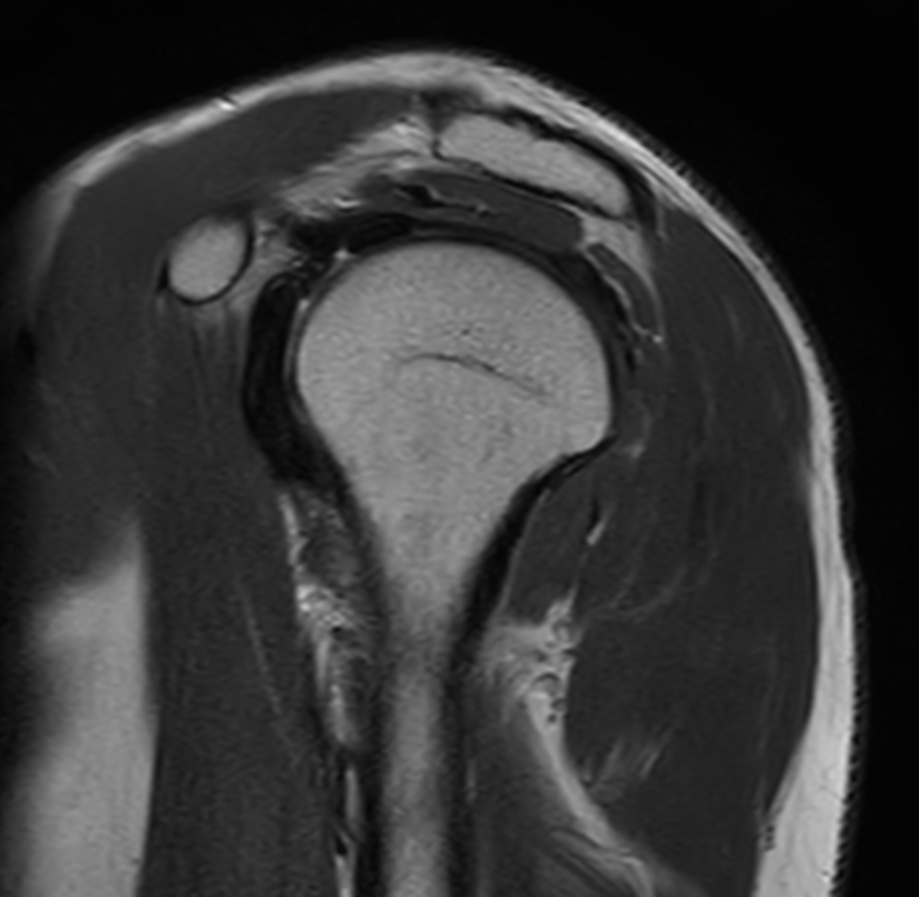

Coronal T1w TSE